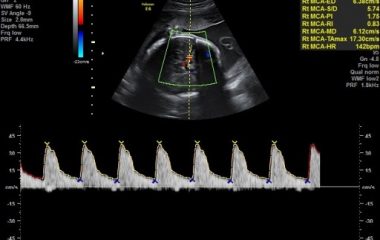

• הערכת זרימות דם